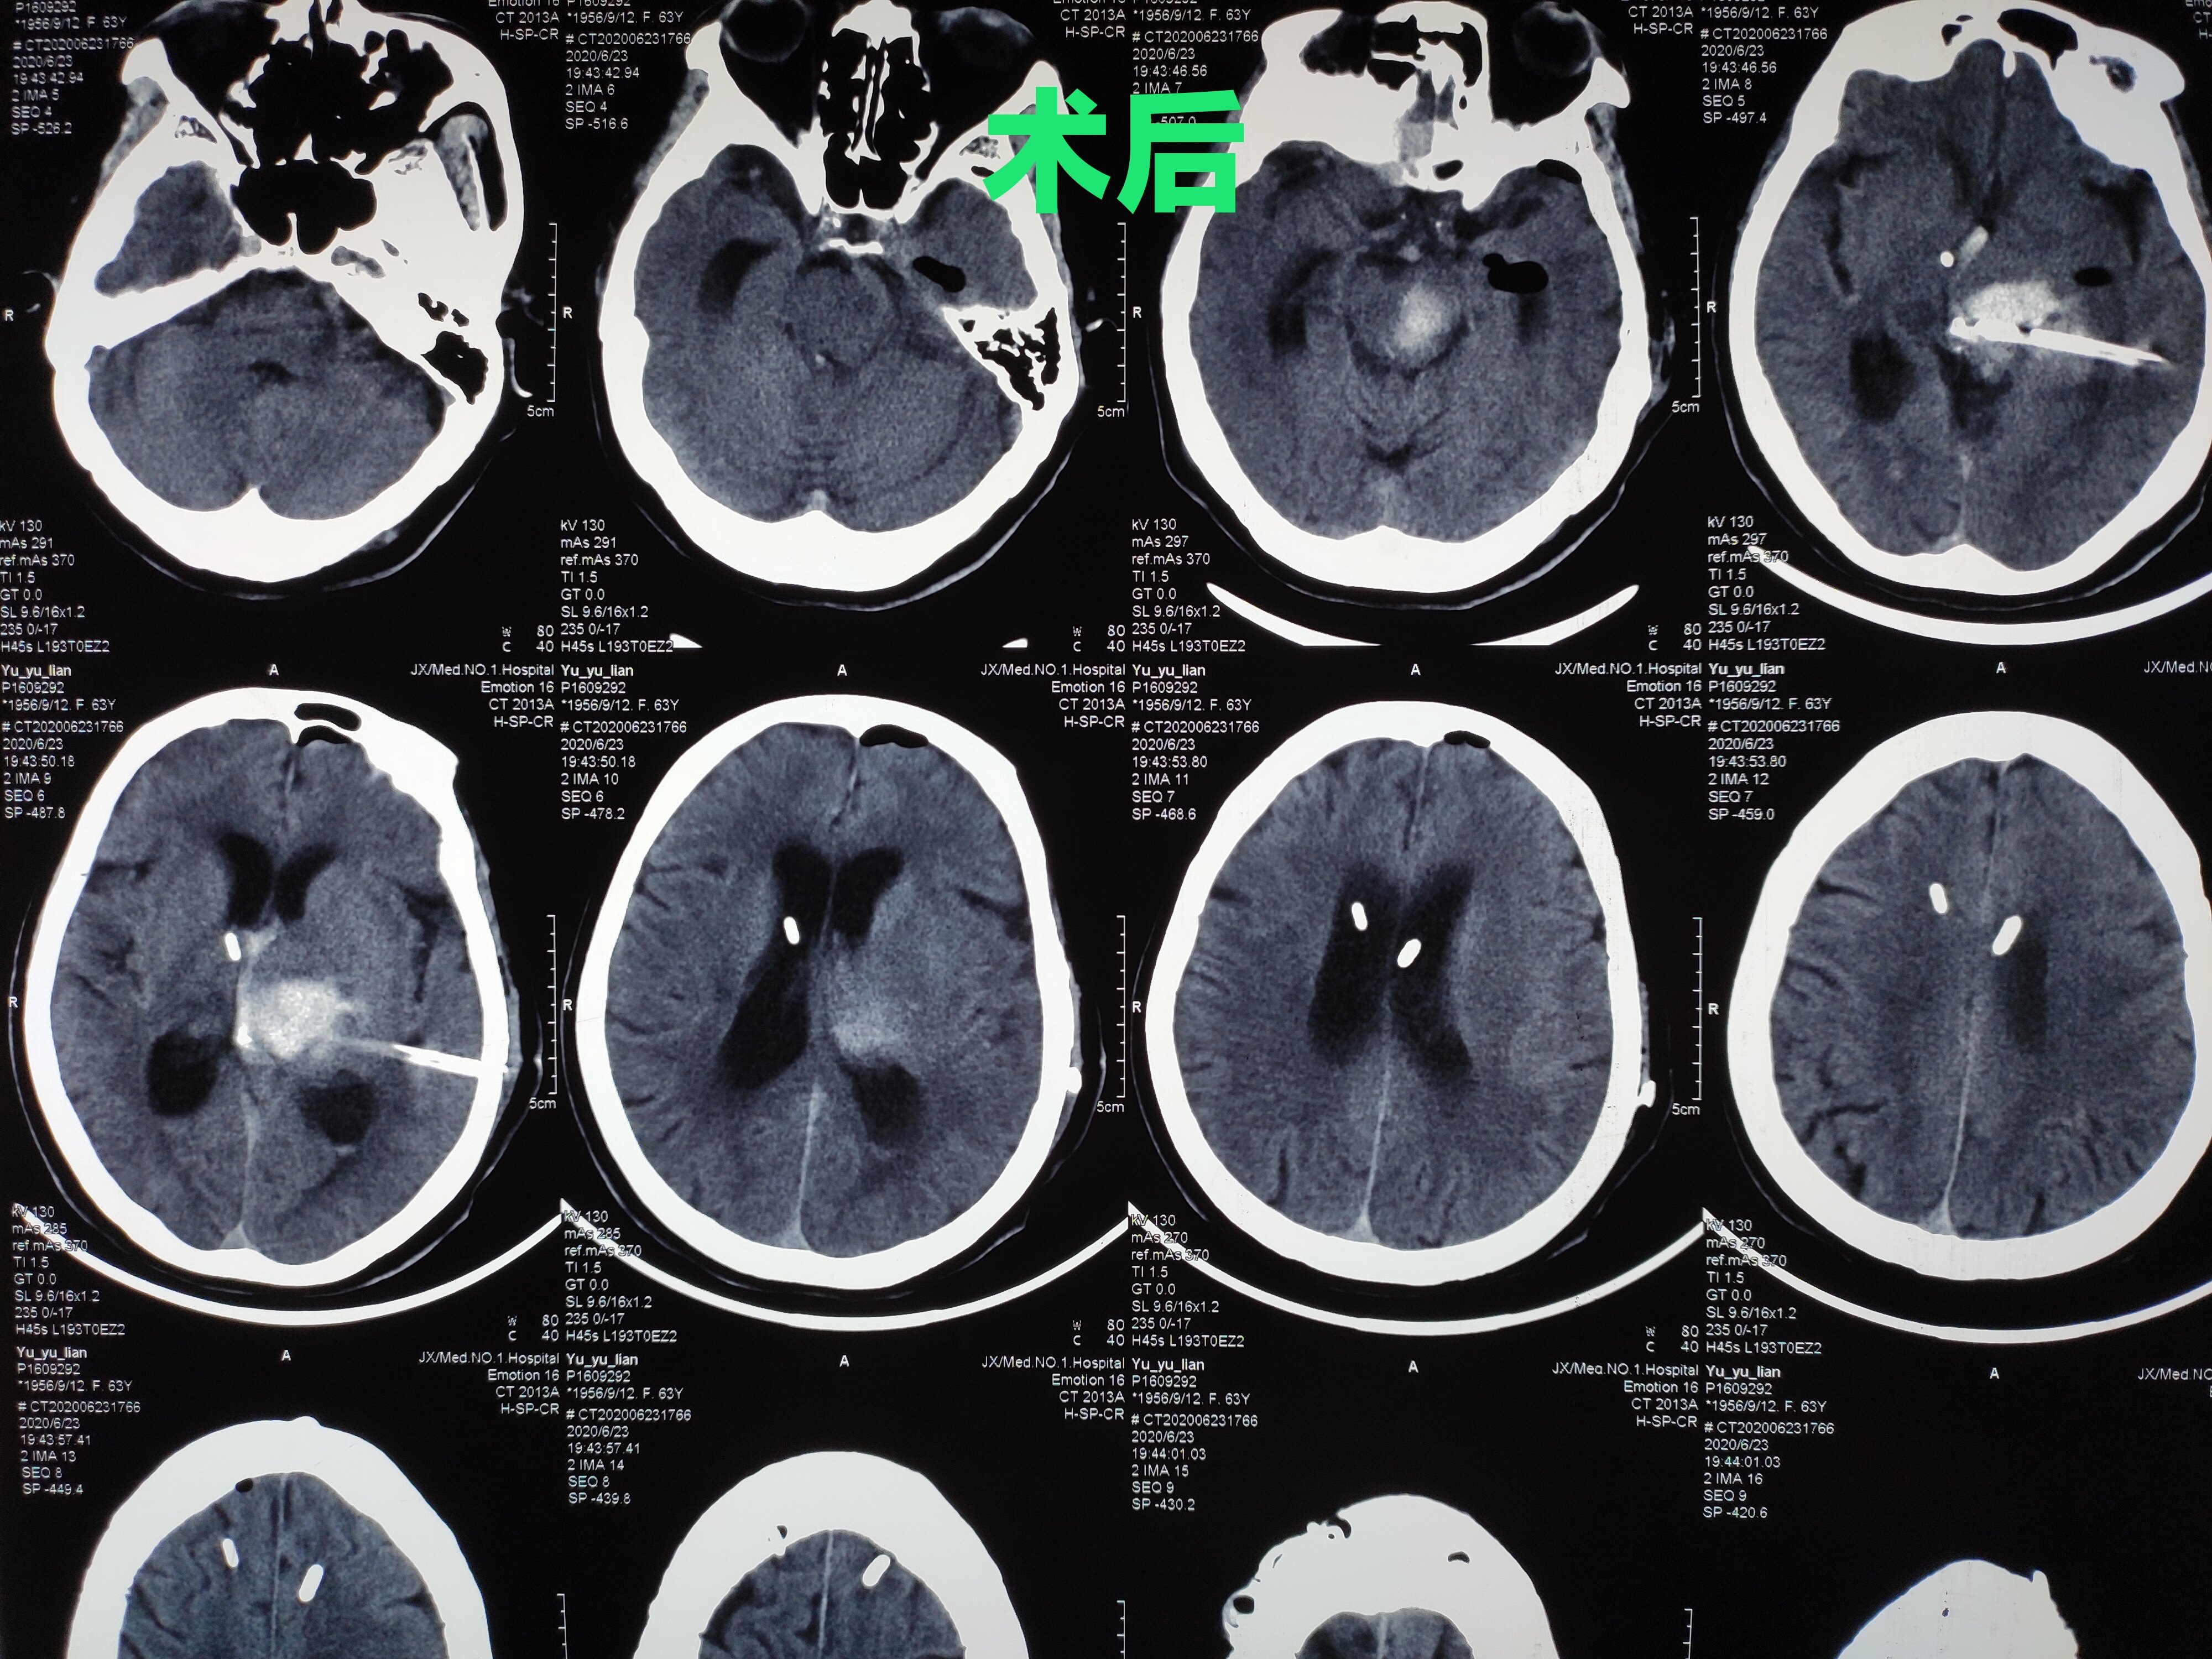

【病例讨论】一例丘脑出血,近两个月艰苦的治疗,感

图片尺寸2592x1944